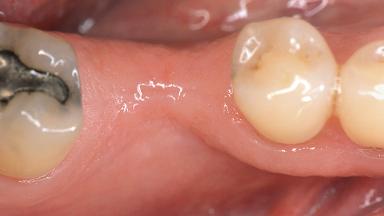

Jaw Mandible

Area Posterior

# of Teeth 1

# of Implants 1

Soft Tissue Grafting Simultaneous